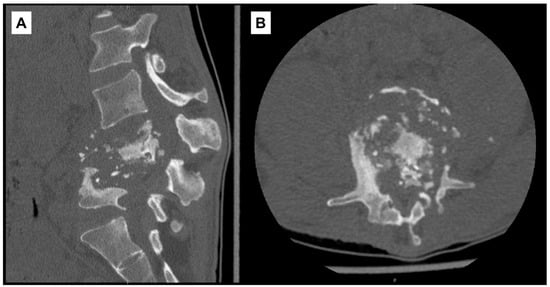

On admission to our institution, RIPE was continued and other antibiotics discontinued. Frank gibbus deformity and tenderness in the lumbar region were noted on exam. Laboratory studies showed leukocytosis (14,500/μL; ref. range: 4000–10,000/μL), anemia (9.2 g/dL), thrombocytosis (621 × 103/μL; ref. range: 140–440 × 103/μL), elevated hsCRP (178.6 mg/L), and elevated sedimentation rate (117 mm/hr). A repeat CT scan of the lumbar spine without contrast on HD2 re-demonstrated prior findings (Figure 2).

Figure 2. Computed-tomography scan of lumbar spine with diffuse destruction of L4–L5 vertebral bodies. (A) Sagittal view. (B) Axial view at L4 vertebral level.